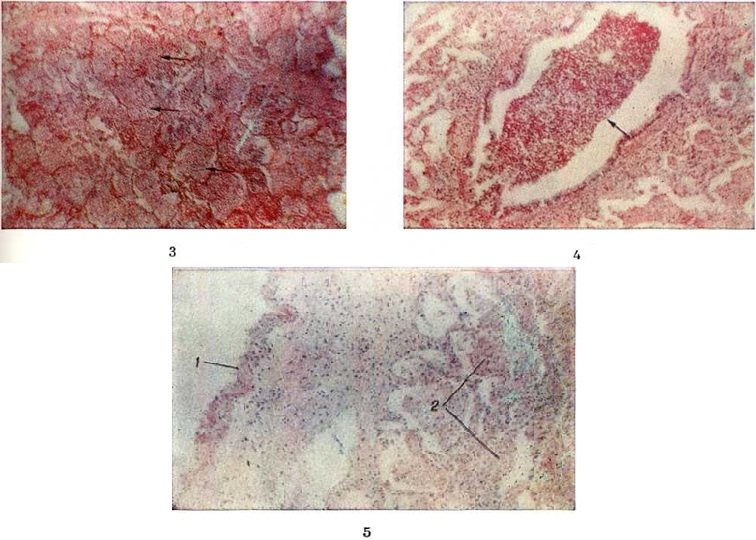

В большей части случаев альтеративный компонент воспаления выражен слабо. Вначале отмечается только полнокровие структурных образований лёгкого, в которых находятся и размножаются бактерии. Вскоре возникает отчётливо выраженная фаза экссудации, которая начинается с выпотевания в полость альвеол плазмы крови — серозной жидкости; затем к ней присоединяется все возрастающее количество нейтрофильных лейкоцитов. При поступлении в очаг воспаления грубодисперсных белков крови происходит выпадение фибрина (рисунок 1). Пролиферативные изменения в подавляющем большинстве острых бактериальных Пневмония выражены незначительно. В том случае, когда бактерии, в частности стафилококки или стрептококки, образуют значительное количество токсинов, возникает некроз клеток экссудата и лёгочной ткани, резко повышается проницаемость кровеносных сосудов.

Стафилококковая Пневмония имеет ряд особенностей. На ранних стадиях заболевания вокруг скоплений стафилококков появляется серозный или чаще серозно-геморрагический экссудат с небольшой примесью нейтрофильных лейкоцитов. В дальнейшем очаги воспаления приобретают характерное зональное строение.

В центре их содержится много стафилококков, возникают некротические изменения (рисунок 3, а), вокруг участков некроза накапливаются лейкоциты, которые фагоцитируют стафилококки. В периферических участках пневмонического очага альвеолы содержат фибринозный или серозный экссудат, в котором нет бактерий. При тяжёлом течении болезни (стафилококковой деструкции лёгких) в местах скоплений стафилококков на значительном протяжении происходит разрушение лёгочной ткани. Макроскопически в лёгких выявляются множественные мелкие, нередко сливающиеся очаги абсцедирующей Пневмония Они красного или темно-красного 4 цвета с желтовато-серыми участками расплавления в центральной части. Позднее здесь формируются абсцессы,. принимающие иногда хронический течение. При распространении инфекционные процесса на плевру и её деструкции возникает сообщение между полостью абсцесса, бронхами и плевральной полостью, развивается пиопневмоторакс (смотри полный свод знаний). Иногда в результате деструкции стенки бронха и проникновения воздуха в интерстиций возникает интерстициальная эмфизема.

Стрептококковая Пневмония имеет много общих черт со стафилококковой. Однако в тяжёлых случаях она характеризуется большей степенью некроза клеток экссудата и лёгочной ткани, а также более выраженной лимфогенной генерализацией процесса.

Для Пневмония при острых вирусных респираторных инфекциях (гриппе, парагриппе, респираторно-синцитиальной и аденовирусной) наиболее характерно поражение эпителия слизистой оболочки дыхательных путей и альвеолоцитов. В результате внутриклеточного размножения вирусов происходит повреждение этих клеток с развитием дистрофических и некротических изменений. При благоприятном течении заболевания через несколько дней в них возникают реактивные изменения в виде уплотнения цитоплазмы вокруг участка повреждения — фуксинофильные включения) (рисунок 3, б). Наряду с этим наблюдаются умеренно выраженные воспалительные изменения слизистой оболочки дыхательных путей с преобладанием нарушений кровообращения в виде полнокровия сосудов, выпотевания серозной жидкости в просвет альвеол и небольших кровоизлияний. Отмечаются также небольшие скопления нейтрофильных лейкоцитов и альвеолярных макрофагов. В результате нарушения образования сурфактанта (смотри полный свод знаний) возникают небольшие ателектазы (смотри полный свод знаний), большей частью неполные,— дистелектазы (рисунок 3, в), что особенно выражено у детей раннего возраста, а также компенсаторное очаговое расширение альвеол в других участках лёгких. Макроскопические изменения при этом незначительны и заключаются в основном в катаральном воспалении дыхательных путей и образовании в лёгких небольших участков уплотнения темно-красного или синюшного цвета. Наиболее характерной чертой вирусной Пневмония является гигантоклеточное превращение поражённых эпителиоцитов.

При гриппе поражённые клетки несколько увеличиваются в объёме, в случае же отторжения превращаются в крупные одноядерные клетки, значительно превышающие по размерам обычные альвеолярные макрофаги (рисунок 3, г). Для парагриппа типичны подушкообразные разрастания, сосочковидные выросты слизистой оболочки. При респираторно-синцитиальной инфекции они ещё более выражены. При аденовирусной Пневмония происходит образование крупных одноядерных клеток (гигантоклеточный метаморфоз альвеолоцитов), а также выраженное накопление экссудата (рисунок 3, д). При выздоровлении происходит регенерация эпителия дыхательных путей. Вначале выявляются недифференцированные уплощённые эпителиальные клетки, располагающиеся обычно в несколько рядов (рисунок 3, е), которые в дальнейшем дифференцируются .

Изменения, сходные с морфологический изменениями при вирусной Пневмония, наблюдаются при микоплазменной Пневмония — респираторном микоплазмозе (смотри полный свод знаний Микоплазменные инфекции). Для неё также типично внутриклеточное размножение возбудителя (рисунок 4), хотя возможно и внеклеточное. Поражения носят характер десквамативной Пневмония при весьма умеренных макроскопических изменениях (цветной рисунок 3—5; 6—10).